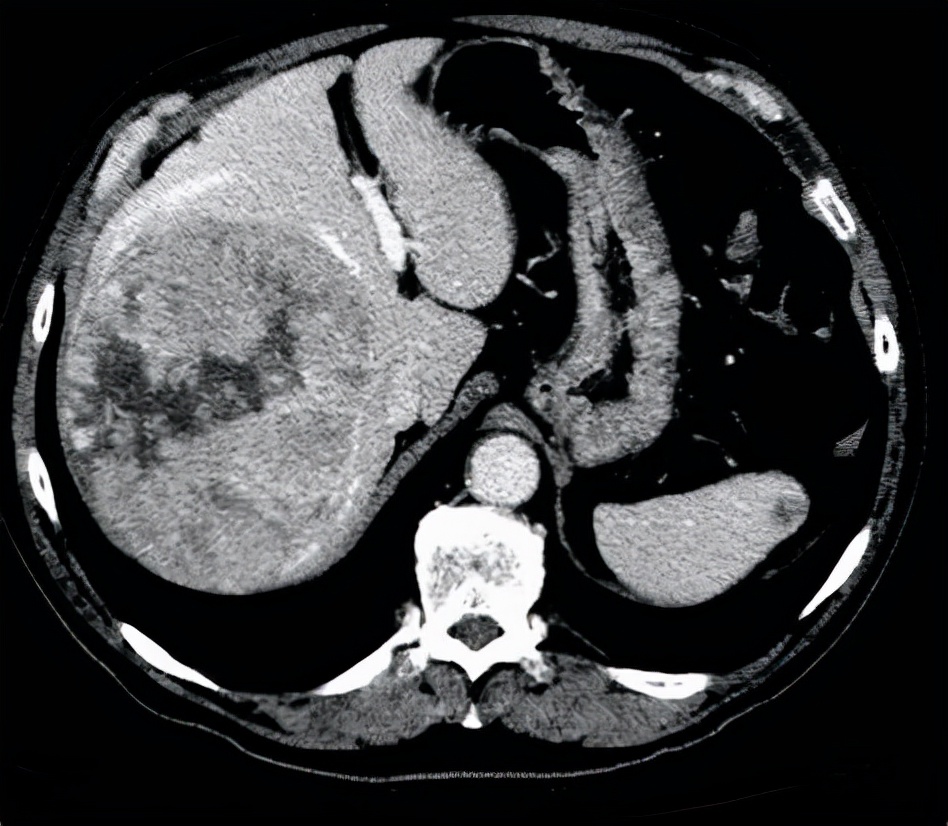

三、肚子越来越大:肝脏问题。

有的患者平时感觉挺健康的,不过在一段时间内,总感觉肚子越来越大了,肚子里面的水可能变多。

这其实是一种非常不容易发现的水肿:腹水。

S如果出现了腹水,很多时候都是由肝脏疾病所导致的,所以腹水常常也都是很难治疗的。

一般来说肝脏淋巴循环受阻或者门脉高压以及低白蛋白血症他们共同作用都会导致腹水的生成,所以治疗起来非常困难。

而且如果因为肝脏疾病出现了全身的水肿,这并不代表肝脏本身的问题,同时也表现出全身营养不良。

肚子太大真的不是什么好事,万一是腹水就麻烦了。